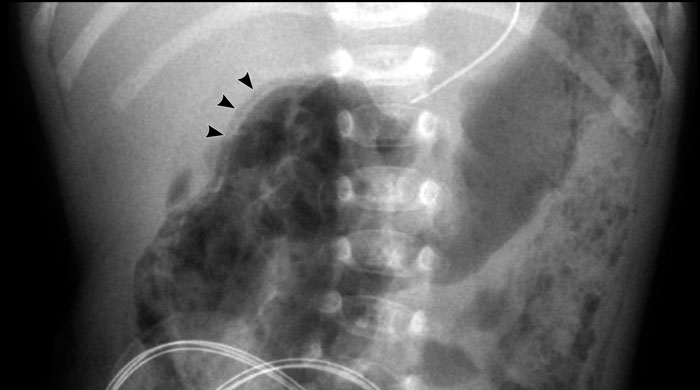

Necrotizing Enterocolitis